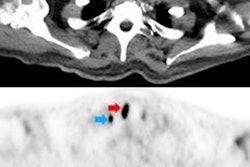

PET/CT scans during annual follow-up visits for patients treated for head and neck squamous cell carcinoma (HNSCC) can lower their risk of death, according to a study published August 1 in JAMA Network Open.

A group led by Jean-Christophe Leclere, MD, of University Hospital of Brest in Brest, France, found that three-year overall survival rates were better in asymptomatic patients who had F-18 FDG-PET/CT scans after treatment compared with conventional chest CT imaging.

After adjusting for covariates (age, sex, comorbidities, primary location, stage, surgeon, year of treatment, and treatment), an analysis revealed a significant association between F-18 FDG-PET/CT and lower risk of death due to recurrence. Specifically, mean three-year overall survival was better in the PET/CT group (72.5%) than in the conventional follow-up group (64.3%), according to the findings.